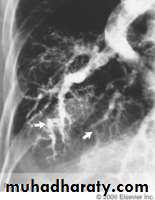

Characterised by hypoxemia, intrapulmonary vascular dilatation and chronic liver disease with portal hypertension.Clinical features; Digital clubbing, cyanosis, spider naevi and a characterized by reduction in arterial oxygen saturation on standing.